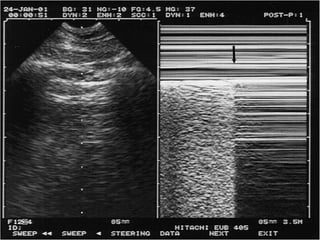

Assessing the IVC

 During inspiration, intrathoracic pressure becomes more

negative, abdominal pressure becomes more positive,

resultant increase in the pressure gradient between the

supra and infra-diaphragmatic vena cava, increases

venous return to the heart.

 Given the extrathoracic IVC is a very compliant vessel

this causes diameter of IVC to decrease with normal

inspiration.

 In patients with low intravascular volume, the inspiration

to expiration diameters change much more than those

who have normal or high intravascular volume.

Estimating theCVP

IVC Diameter (mm) % collapse Estimated CVP (cm

H2O)

<20 >50 5

<20 <50 10

>20 <50 15

>20 0 20

Right atrial pressures, representing central venous pressure, can be estimated

by viewing the respiratory change in the diameter of the IVC.

American society of Echocardiography

2010 guidelines

Assessing the IVC During inspiration, intrathoracic pressure becomes more negative, abdominal pressure becomes more positive, resultant increase in the pressure gradient between the supra and infra-diaphragmatic vena cava, increases venous return to the heart.  Given the extrathoracic IVC is a very compliant vessel this causes diameter of IVC to decrease with normal inspiration.  In patients with low intravascular volume, the inspiration to expiration diameters change much more than those who have normal or high intravascular volume.

Estimating theCVP IVC Diameter(mm) % collapse Estimated CVP (cm H2O) <20 >50 5 <20 <50 10 >20 <50 15 >20 0 20 Right atrial pressures, representing central venous pressure, can be estimated by viewing the respiratory change in the diameter of the IVC.